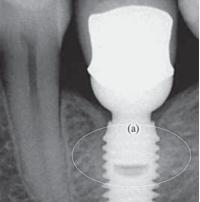

Non ci sono differenze statisticamente significative nel comportamento clinico tra impianti singoli avvitati e impianti singoli cementati. Questo è il risultato al quale sono arrivati Paolo Vigolo e altri tre specialisti della clinica universitaria di Padova alla fine di uno studio durato dieci anni. La ricerca, pubblicata pochi mesi fa (Cemented versus screw-retained implant-supported single-tooth crowns: a 10-year randomised controlled trial. Eur J Oral Implantol. 2012 Winter;5(4):355-64) è particolarmente interessante per il tipo di protocollo usato, oltre che per la sua lunga durata. Gli autori, infatti, hanno scelto un metodo di ricerca split-mouth (letteralmente bocca divisa) in cui ogni paziente ha ricevuto un impianto cementato su un lato e uno avvitato sull'altro lato (scelti in modo casuale). Questo riduce di molto il rischio che i risultati siano influenzati da variabili individuali come la forza muscolare anche se può continuare a giocare un ruolo il lato di masticazione preferenziale. I punti deboli della ricerca sono il numero di pazienti limitato a 16 e la differenza di sede anatomica tra un paziente e l'altro (gli impianti sostituivano premolari o molari).

I parametri valutati dagli autori sono stati la durata dell'impianto, le complicazioni, l'altezza dell'osso marginale e lo stato dei tessuti perimplantari. Nel complesso, la percentuale di successo è stata elevata, poiché sono stati persi solo due impianti (dopo 5 anni nello stesso paziente) e non si sono registrate complicazioni. La perdita media di osso è stata di 1,1 mm in linea con quanto ampiamente documentato in letteratura senza differenze significative tra i due tipi di impianto e così pure per le condizioni dei tessuti molli. Le ricerche di questo tipo non abbondano in letteratura, nonostante il problema non sia di poco conto; per chi vuole approfondire, segnaliamo l'articolo Peri-implant bone loss in cement- and screw-retained prostheses: systematic review and meta-analysis (de Brandão ML et al, J Clin Periodontol. 2013 Mar;40(3):287-95) in cui vengono passati in rassegna quelli di migliore qualità metodologica. Le conclusioni per quanto riguarda la perdita di osso marginale, l'unico parametro considerato, non indicano differenze statisticamente significative: 0,53 mm per gli impianti cementati e 0,89 per quelli avvitati.